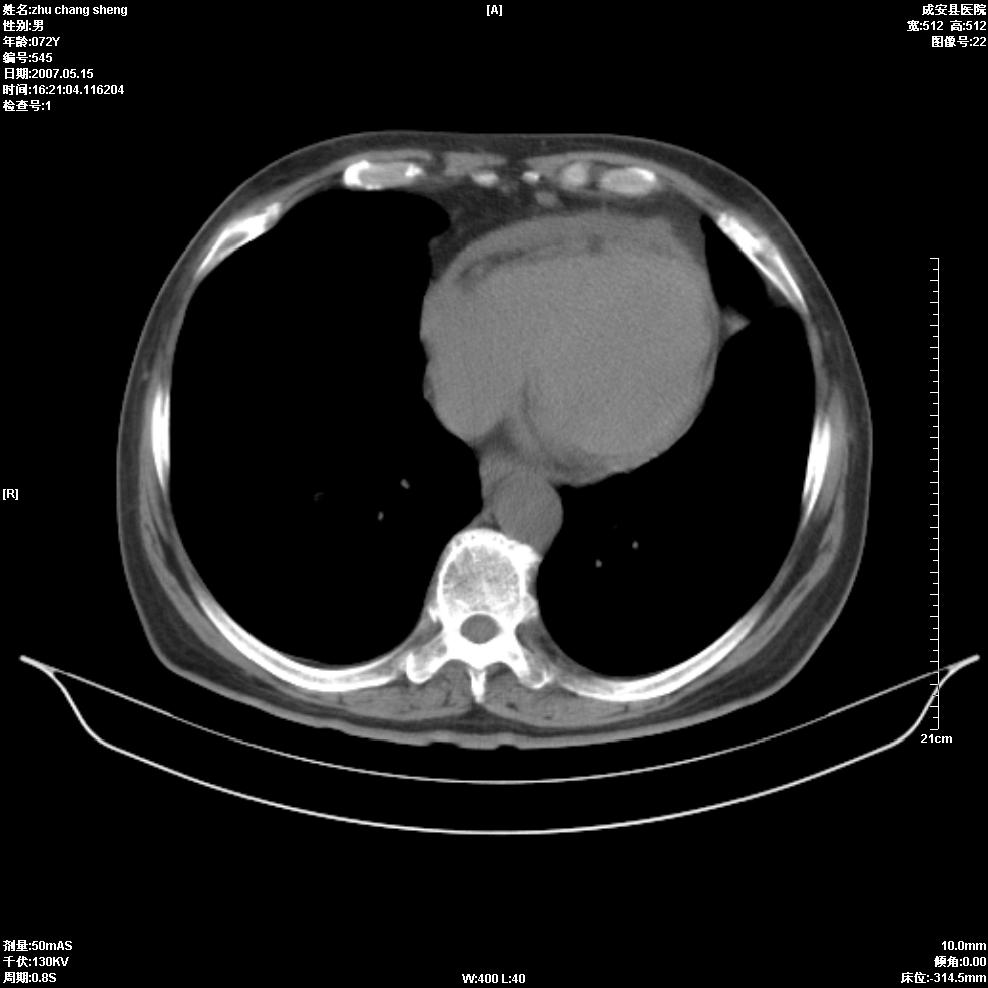

以下是引用医博云天在2007-5-15 19:10:00的发言:[br]心包积液,胸腔积液,心影增大,左心为主。

以下是引用zhangzhongshou在2007-5-15 20:21:00的发言:[br]心包积液可以肯定有,肿块显示不清,建议增强或mri检查。

以下是引用jinning在2007-5-15 21:06:00的发言:[br]心包积液可以肯定,建议增强或mri检查吧!

以下是引用拾荒者在2007-5-15 22:28:00的发言:[br]心包膜增厚,有少量积液,右室前壁示均匀软组织密度影,边界欠清,建议增强扫描或mri检查与室壁瘤鉴别。

以下是引用还珠格格在2007-5-19 9:50:00的发言:[br]病人与5月18日 做了核磁增强扫描 确诊为前上纵隔侵袭性胸腺瘤。